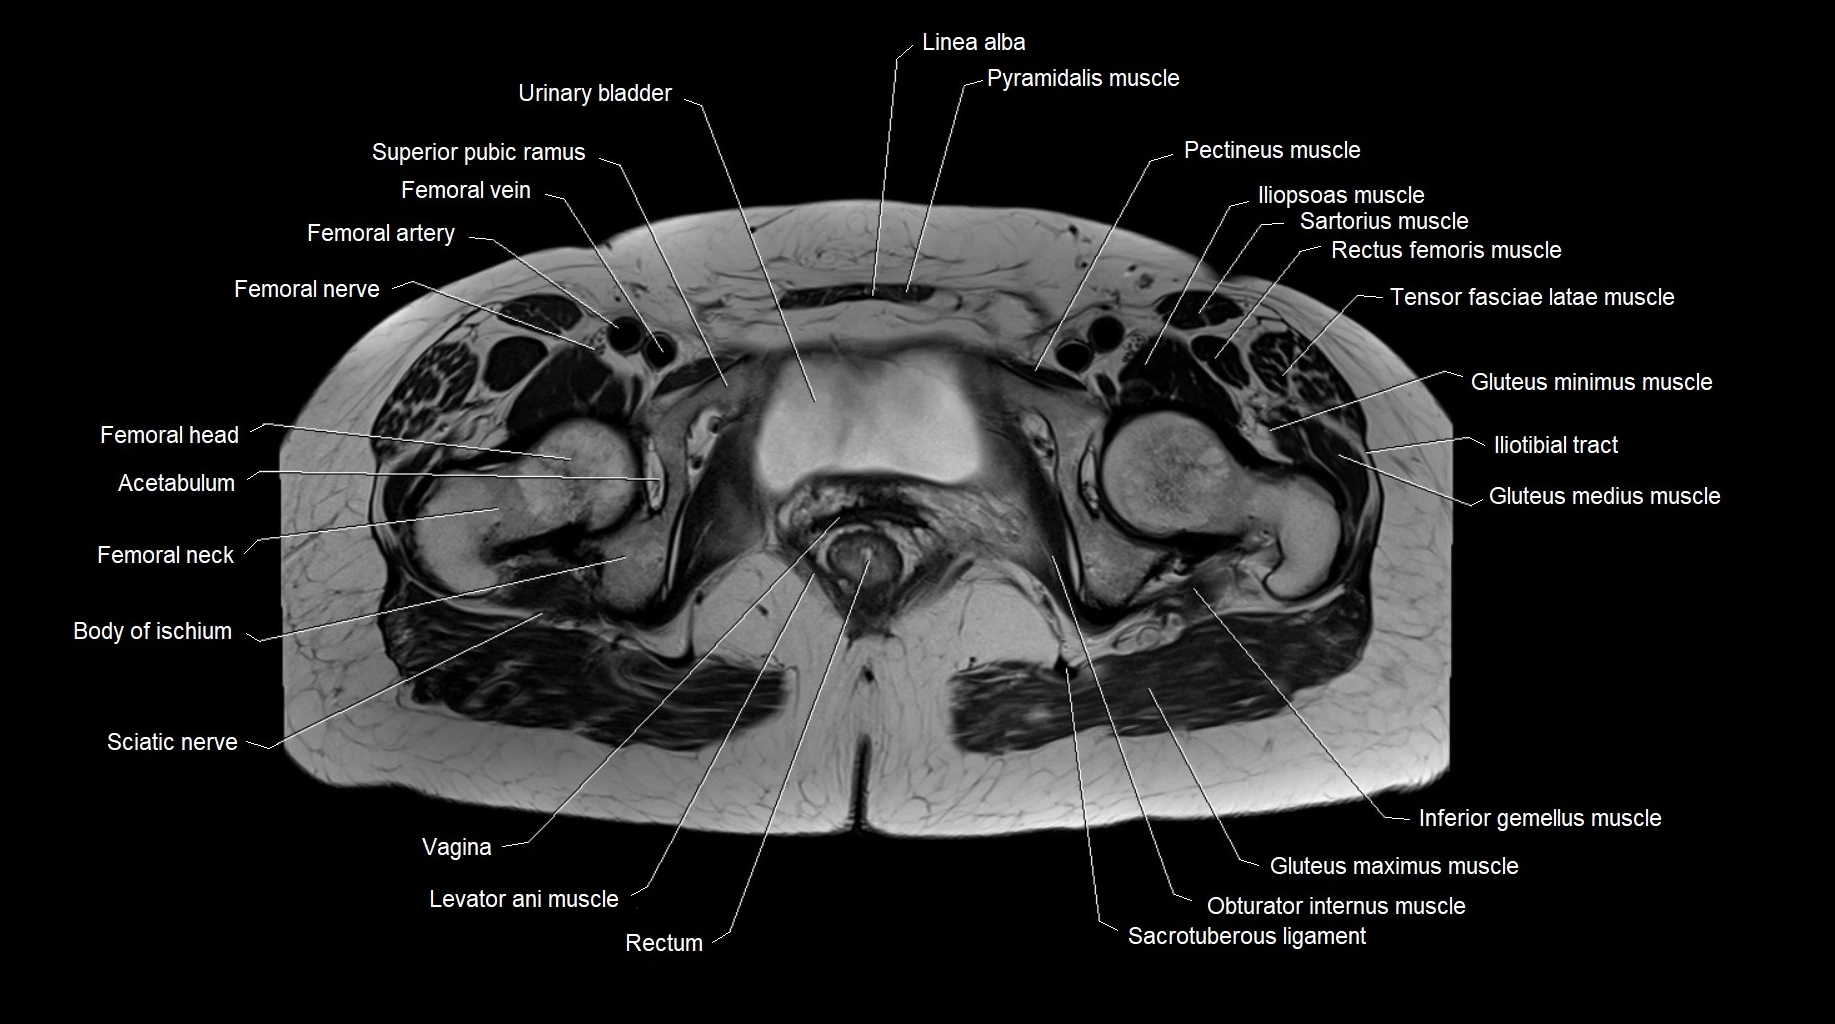

- Acetabulum

- Body of ischium

- Femoral artery

- Femoral nerve

- Femoral vein

- Head of femur

- Iliopsoas muscle

- Iliotibial tract

- Inferior gemellus muscle

- Levator ani muscle

- Obturator internus muscle

- Pectineus muscle

- Rectus femoris muscle

- Sacrotuberous ligament

- Sciatic nerve

- Tensor fasciae latae muscle

- Urinary bladder

- Vagina